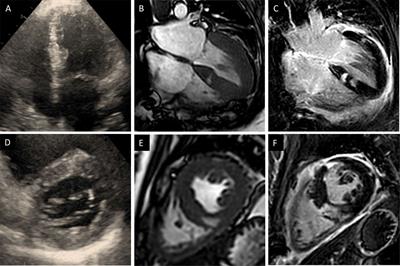

Case report: Heart transplant for persistent right heart failure after complete surgical repair and percutaneous closure of post-myocardial infarction ventricular septal rupture